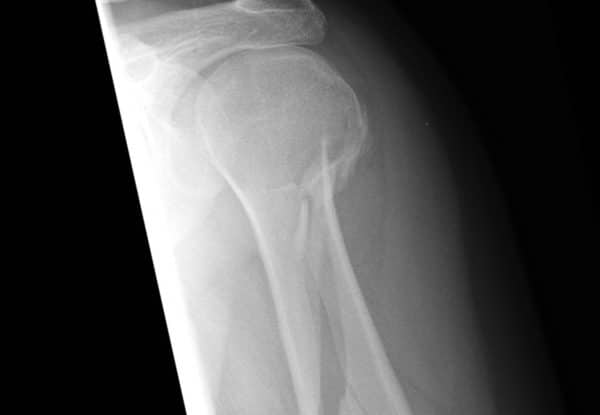

FRACTURES DES MEMBRES

Les fractures des os des membres sont d’une relative grande fréquence et sont le plus souvent la conséquence d’une chute. En aéronautique civile les risques de chute ne manquent pas lors de l’embarquement, de turbulences en vol ou lors de crash. Les complications immédiates sont rares et ne mettent pas le pronostic vital en jeu.

FRACTURE FERMÉE :

L’os brisé se trouve toujours à l’intérieur du membre qui est déformé.

FRACTURE OUVERTE :

L’os brisé a traversé les tissus et la peau, et pointe à l’extérieur du membre. La présence d’une plaie ou d’un trou à proximité d’un foyer de fracture suffit à dire que la fracture est ouverte.